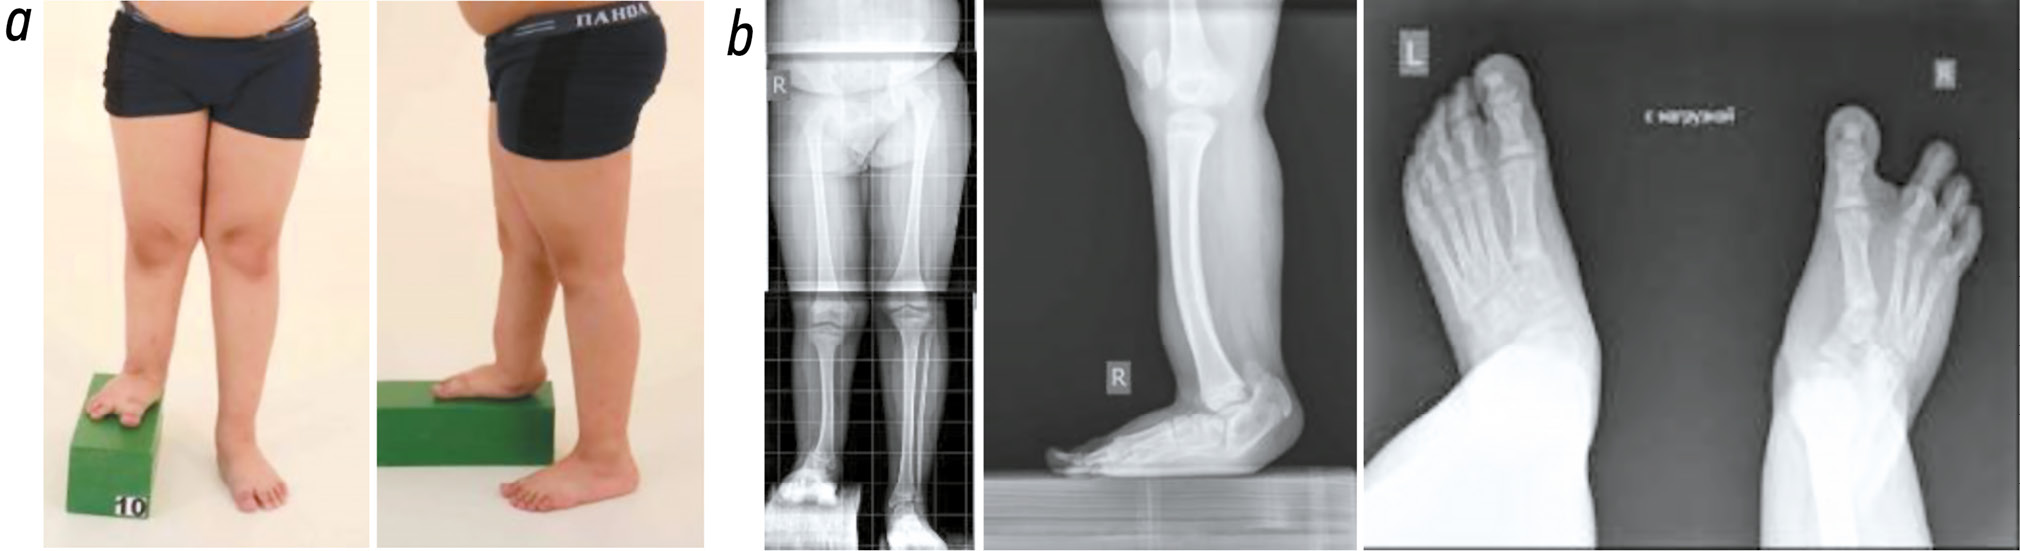

The Ilizarov method used for this patient enabled safe and reliable limb lengthening, reconstruction, and preservation, instead of amputation. Three years after the treatment, the patient was satisfied with the outcome and was walking independently in orthopedic footwear with a custom insole (Fig. 5). A valgus deviation of the hindfoot up to 10–12° was noted. Full range of motion was preserved in the knee joint, and ankle joint mobility was measured at 25° (compared to 10° preoperatively).

Fig. 5. Photographs (a) and radiographs (b) of the right tibia and foot three years after the treatment.

The evaluation criteria for the tibial lengthening stage included the external fixation index, amount of lengthening (cm, %), the Lascombes classification [22], and the Association for the Study and Application of the Method of Ilizarov (ASAMI) score [23]. Functional outcome was assessed using the ASAMI criteria and the Gillette questionnaire. The total lengthening achieved was 10 cm, corresponding to 43.4% of the original tibial length. According to the Lascombes classification, the result of lengthening was categorized as grade I. The bone lengthening was rated as “excellent” by the ASAMI score, and the overall functional outcome was rated as “good.”

According to the Gillette questionnaire, the patient’s level of functional mobility improved from level 3 preoperatively to level 9 postoperatively.